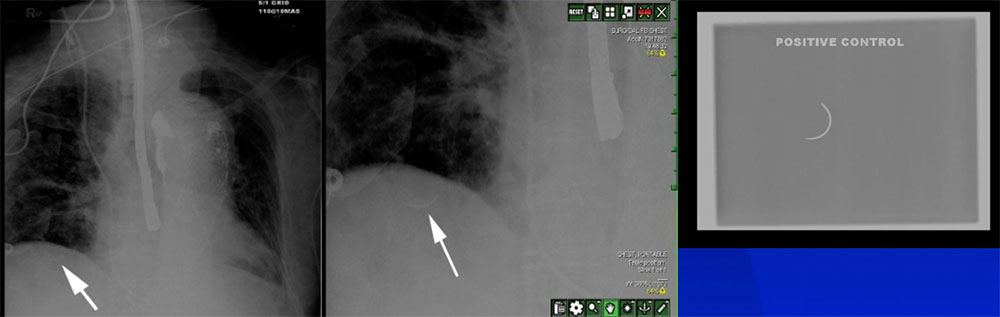

Intraoperative Radiography

Intraoperative Radiography

Intraoperative Radiography

Intraoperative Radiography

Intraoperative Radiography  |

Intraoperative Radiography  |